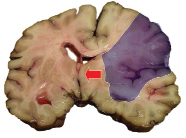

Udar mózgu niedokrwienny- rozległy zawał mózgu w obszarze tętnicy środkowej mózgu z masywnym obrzękiem półkuli i towarzyszącym przemieszczeniem struktur środkowych (strzałka)

Fot. www.wikipedia.pl